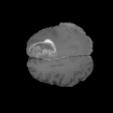

To better retain the deep features of an image and solve the sparsity problem of the end-to-end segmentation model, we propose a new deep convolutional network model for medical image pixel segmentation, called MC-Net. The core of this network model consists of four parts, namely, an encoder network, a multiple max-pooling integration module, a cross multiscale deconvolution decoder network and a pixel-level classification layer. In the network structure of the encoder, we use multiscale convolution instead of the traditional single-channel convolution. The multiple max-pooling integration module first integrates the output features of each submodule of the encoder network and reduces the number of parameters by convolution using a kernel size of 1. At the same time, each max-pooling layer (the pooling size of each layer is different) is spliced after each convolution to achieve the translation invariance of the feature maps of each submodule. We use the output feature maps from the multiple max-pooling integration module as the input of the decoder network; the multiscale convolution of each submodule in the decoder network is cross-fused with the feature maps generated by the corresponding multiscale convolution in the encoder network. Using the above feature map processing methods solves the sparsity problem after the max-pooling layer-generating matrix and enhances the robustness of the classification. We compare our proposed model with the well-known Fully Convolutional Networks for Semantic Segmentation (FCNs), DecovNet, PSPNet, U-net, SgeNet and other state-of-the-art segmentation networks such as HyperDenseNet, MS-Dual, Espnetv2, Denseaspp using one binary Kaggle 2018 data science bowl dataset and two multiclass dataset and obtain encouraging experimental results.